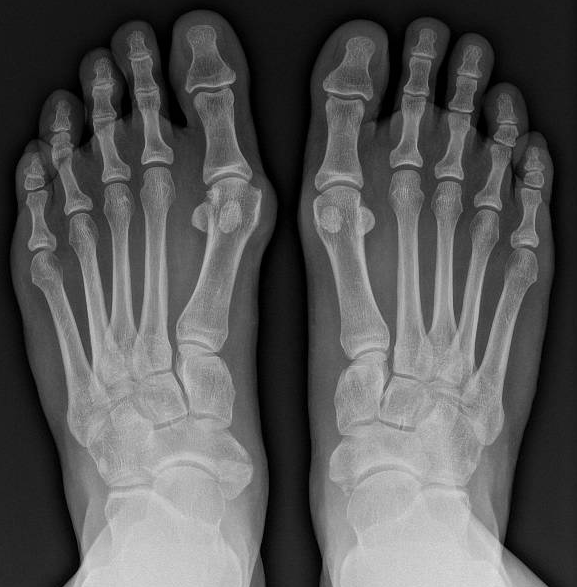

De diagnose wordt gesteld aan de hand van een klinisch onderzoek in combinatie met de nodige staande radiografieën van de beide voeten.